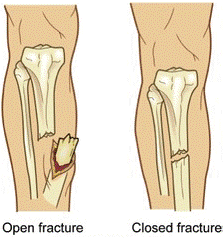

Ясны хугаралыг хэлбэрээр нь:

Ил болон далд гэж ангилдаг.

• Ил хугарал гэдэг нь яс хугарч хугарлын үзүүрүүд нь арьсыг цоолон ил гарч харагдаж байгаа хугарал юм.

• Далд хугарал гэдэг нь хүчтэй доргилт, битүү гэмтлийн улмаас арьсанд шарх үүсгэлгүй яс хугарахыг хэлнэ. Үүнийг танихад төвөгтэй байдаг. Учир нь хугарлын үзүүрүүд нүдэнд ил харагдахгүй, тэр орчмын зөөлөн эдүүд хавдаж, улайсан, өвдөлт ихтэй байдаг тул үзлэг хийхэд төвөгтэй байдаг.